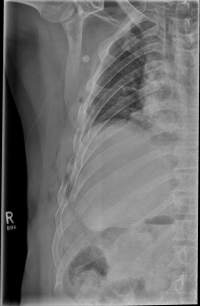

Rib Fractures

The rib fracture is a common injury to the chest. It occurs frequently in (car) accidents, falls during cycling and contact sports. Due to their anatomical position, especially the 4th - 9th ribs are affected.

As a rule, the rib fracture is diagnosed by X-ray. In severe cases or ambiguous X-ray findings, a layer imaging, for example computer tomography (CT), can also be performed.

After about six weeks, the fractures have healed and can only be seen on X-rays. As a rule, a subsequent limitation for the patient usually does not arise.